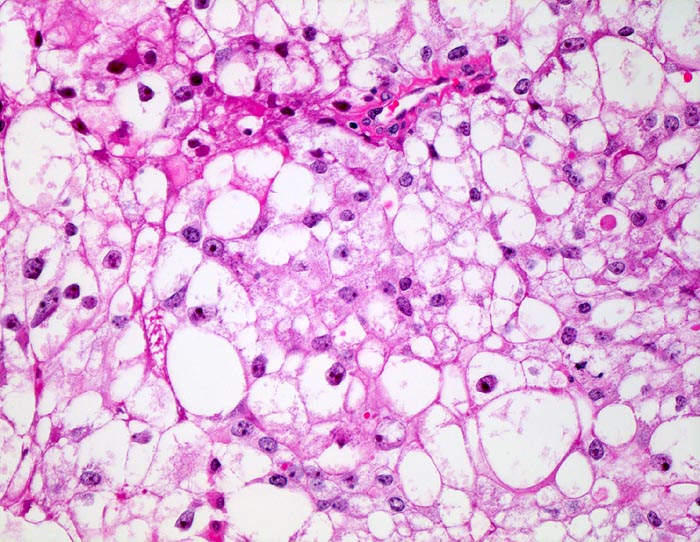

Hellzelliges Nierenzellkarzinom, Urin

Typisch für das Nierenzellkarzinom sind relative grosse ein- oder mehrkernige atypische Zellen mit exzentrisch gelegenem Zellkern, plumpen Nukleolen und vakuolisiertem Zytoplasma. Der zytologische Nachweis wird dadurch erschwert, dass die Zellen auf ihrem Weg in die Harnblase degenerieren. Der Kern ist oftmals pyknotisch und das Zytoplasma in Auflösung und eosinophil granuliert. Differentialdiagnostisch muss an Tubulus- oder Sammelrohrepithelien gedacht werden.